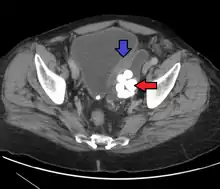

- Bladder diverticula are balloon-like growths on the bladder commonly associated with chronic outflow obstruction, such as benign prostatic hyperplasia in older males. Usually found in pairs on opposite sides of the bladder, bladder diverticula are often surgically removed to prevent infection, rupture, or even cancer.

Bladder diverticula containing stones: the bladder wall is thickened due to possible transitional cell carcinoma.- Bladder diverticula as seen on ultrasound with doppler[18]